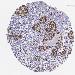

SKIN CANCER - Protein expressioni

A mouse-over function shows sample information and annotation data. Click on an image to view it in a full screen mode. Samples can be filtered based on level of antibody staining by selecting one or several of the following categories: high, medium, low and not detected. The assay and annotation is described here.

Each image is clickable and will lead to virtual microscopy that enables deeper exploration of all samples and also displays staining intensity scores, fraction scores and subcellular localization as well as patient and tissue information for each sample.

Antibody HPA000287

Antibody HPA001894

Staining

High

Medium

Low

Not detected

Intensity

Strong

Moderate

Weak

Negative

Quantity

>75%

75%-25%

<25%

None

Location

Nuclear

Cytoplasmic/membranous

Cytoplasmic/membranous,nuclear

Squamous cell carcinoma, NOS

Basal cell carcinoma